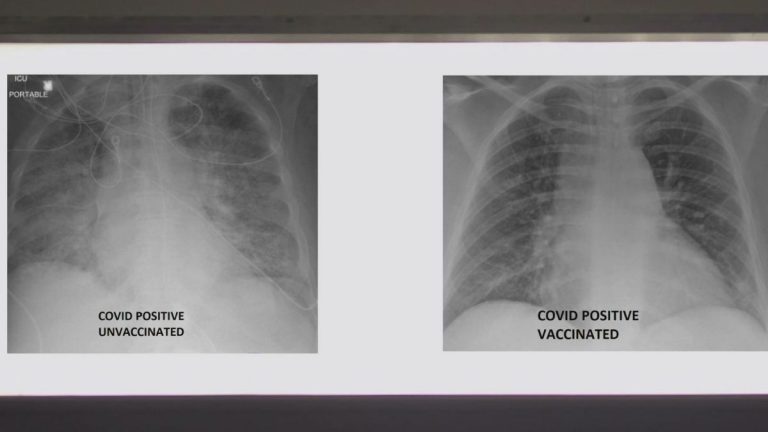

Radiografías revelan diferencias entre pulmones con y sin vacuna